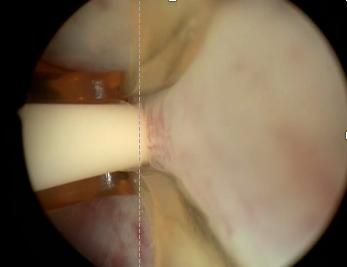

水蒸气消融手术是利用射频能量产生水蒸气储存热能,手术中将注射针插入前列腺组织,利用103度水蒸气对前列腺进行消融。 每针插入8秒产生208cal的能量,可将前列腺组织加热到70度,平均每针消融前列腺组织18g。

一般手术平均注射5针,对于大体积前列腺可注射到8~10针。随后前列腺组织将产生凝固坏死。 在术后1~3个月后,坏死的前列腺组织将逐步脱落随尿液排出,形成自然通道。